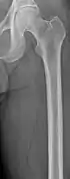

The diagnostic examination of a person with suspected multiple myeloma typically includes a skeletal survey. This is a series of X-rays of the skull, axial skeleton, and proximal long bones. Myeloma activity sometimes appears as "lytic lesions" (with local disappearance of normal bone due to resorption) or as "punched-out lesions" on the skull X-ray ("raindrop skull"). Lesions may also be sclerotic, which is seen as radiodense.[64] Overall, the radiodensity of myeloma is between −30 and 120 Hounsfield units (HU).[65] Magnetic resonance imaging is more sensitive than simple X-rays in the detection of lytic lesions, and may supersede a skeletal survey, especially when vertebral disease is suspected. Occasionally, a CT scan is performed to measure the size of soft-tissue plasmacytomas. Bone scans are typically not of any additional value in the workup of people with myeloma (no new bone formation; lytic lesions not well visualized on bone scan).

Femur with multiple myeloma lesions

Same femur before myeloma lesions for comparison